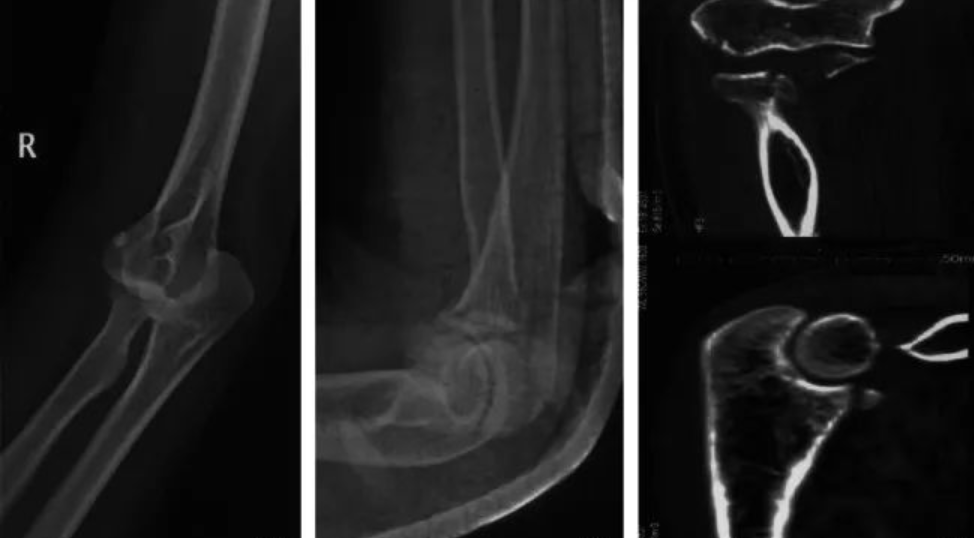

“肘关节恐怖三联征”——诊疗思路更清晰的秘籍!